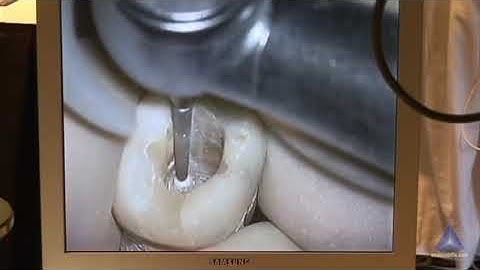

Radix entomolaris | Easy technique